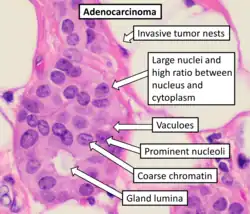

- Adenocarcinoma

- (adeno = gland) Refers to a carcinoma featuring microscopic glandular-related tissue cytology, tissue architecture, and/or gland-related molecular products, e.g., mucin.